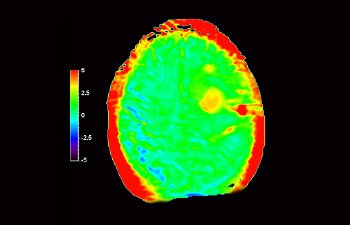

Maggiore affidabilità diagnostica in neuro-oncologia